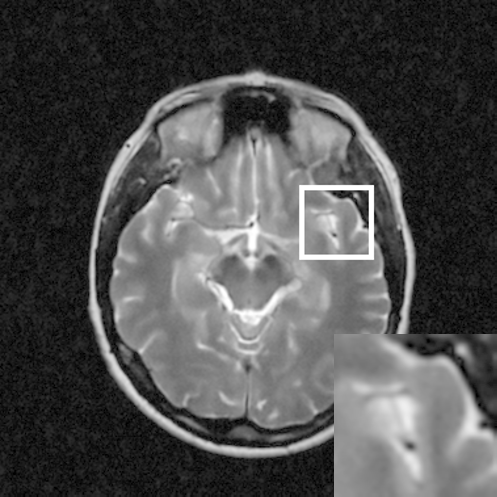

Figure 8: Reconstruction results for 25% cartesian sampling. (a) Original. (b)-(h) Reconstructed images. (i)-(n) The errors of six CSMRI methods.

As shown in Figs. 7, 8 and 9, Sparse MRI and DLMRI have a lot of unpleasant artifacts, Residual learning and U-net can eliminate most of artifacts, but are not ideal for restoring image details. However, the proposed method can reconstruct better MR images, which outperforms other competitive methods in visualization of structures reconstruction and artifacts removal. Meanwhile, we can see from the absolute error residuals for three sampling experiments that the proposed MDN algorithm restores a finer detail structure than other algorithms. Moreover, we present the PSNR and SSIM values in Table I for different algorithms, sampling masks and sampling rates. It is demonstrated that the proposed method provides better reconstruction performance and visual results than other competitive methods. We can also see the obvious improvement of all algorithms over zero-filling both in visualization. In particular, a higher SSIM value of Sparse MRI appears when using 30% variable density random sampling, however, Sparse MRI generates more artifacts than the proposed MDN.